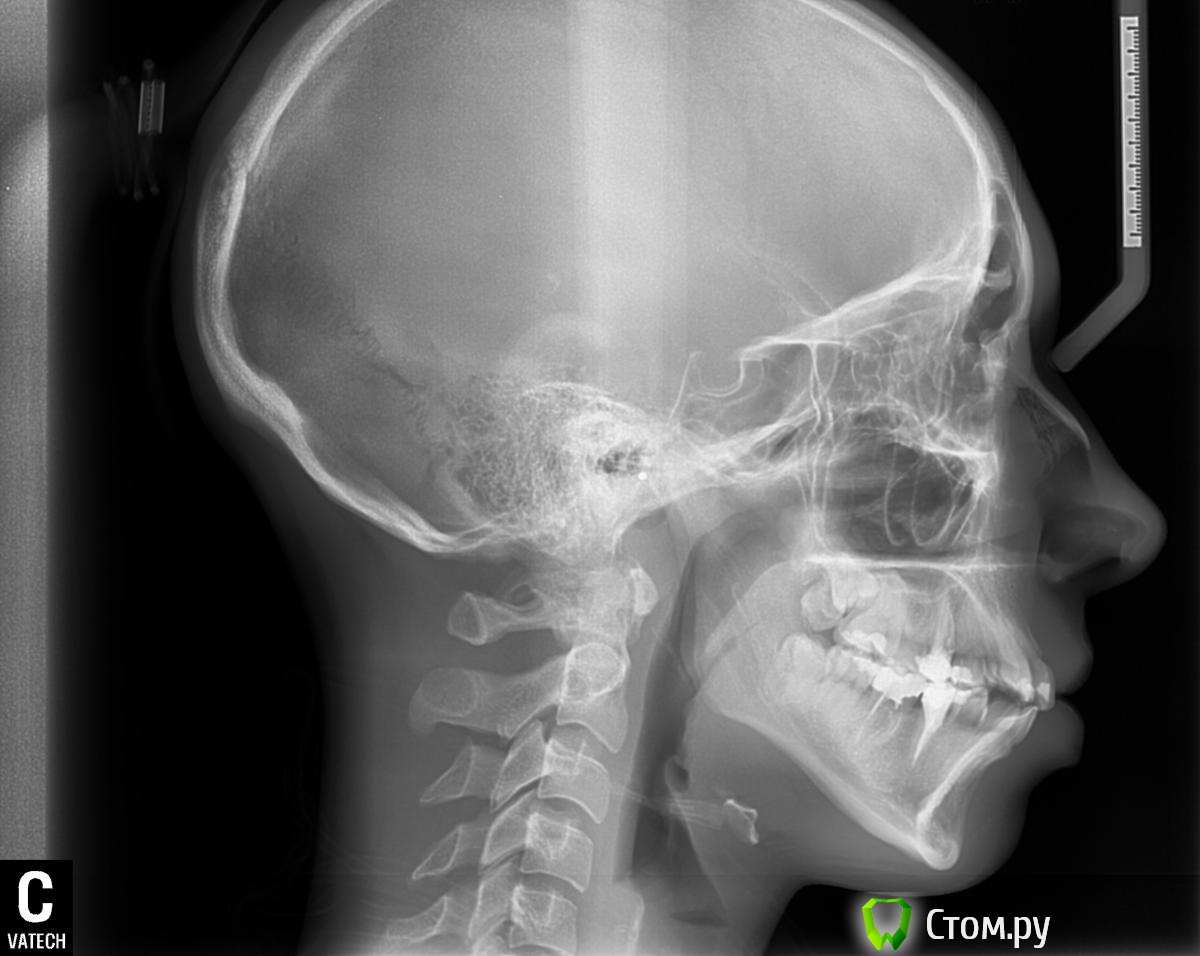

IgorH Опубликовано 7 апреля, 2014 Поделиться Опубликовано 7 апреля, 2014 Добрый деньИнтресует Ваше мнение по поводу необходимости удаления премоляров по моим расчетам-1 скелетный класс,SNA=80SNB=74ANB=6Ось Y=77SN-MP=46вертикальный тип роста WITS меньше 1 мм поэтому 1 скелетный класс по дуге:на вч дефицит места 11 ммна нч 8 ммуглы резцов к плоскостям челюстейвч 115 нч 102 межрецовый угол 107 согласно треугольникам Фастлайта,для первого класса углы 110/90значит нужно сделать навч 115 ретрузию до 110 на нч 102 ретрузию до 90 итого:дефицит места,протрузия,выпуклый профиль,зубы вне дуги Все говорит о том,что необходимо лечение с удалением 4 зубов,интересует Ваше мнение Заранее Благодарю Ссылка на комментарий

IgorH Опубликовано 18 апреля, 2014 Автор Поделиться Опубликовано 18 апреля, 2014 Согласен,по интернету диагностику проводить несколько неудобно)по поводу сохранения торка при анализе ТРГ, я определил 1 скелетный классWITS меньше 1 мм для 1 класса -согласно треугольников Фастлайта,мы стремимся к соотношению углов 110-90(угол ось резца,по отношению к плоскости вч и нч соответственно) у пациентки-вч 115 градусов,за все время лечения мне нужно потерять,всего 5 градусов наколонапосле удаления 5 зубов, зубы вч должны сами потерять эти градусы,но чтобы не дать им потерять больше,на этапе выравниваня,до одевания пружин,я планирую использовать брекеты с высоким торкомкогда резцы по оси станут правильно ,тогда я зафиксирую наклон,используя особенности действия пружины хотя на вч анкораж минимальный,все равно есть риск потерять больше чем 5 градусов,на этапе выравниванияИМХО 1 Ссылка на комментарий